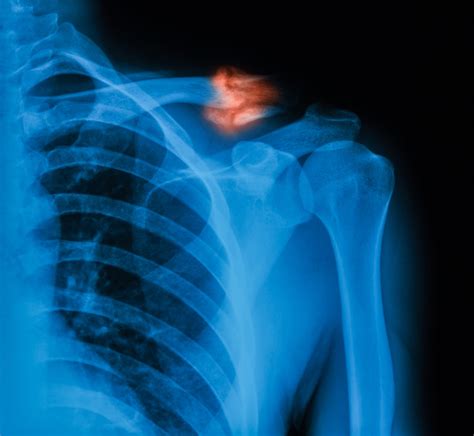

• Radiographic Evidence: An X-ray is the gold standard. A doctor looks for "bridging callus," which indicates that new bone has grown across the fracture site.

Achieving a healed broken clavicle is a milestone that signifies the end of a difficult period, but it is also a transition toward long-term maintenance. By respecting the timeline of bone regeneration and committing to the necessary physical therapy, you ensure that your shoulder remains stable and strong for years to come. Listen to your body, rely on objective diagnostic tools like X-rays to guide your progress, and do not rush the transition back to high-intensity activities. With the right care and patience, most individuals return to their full baseline of strength and daily function, putting the injury firmly in the past.